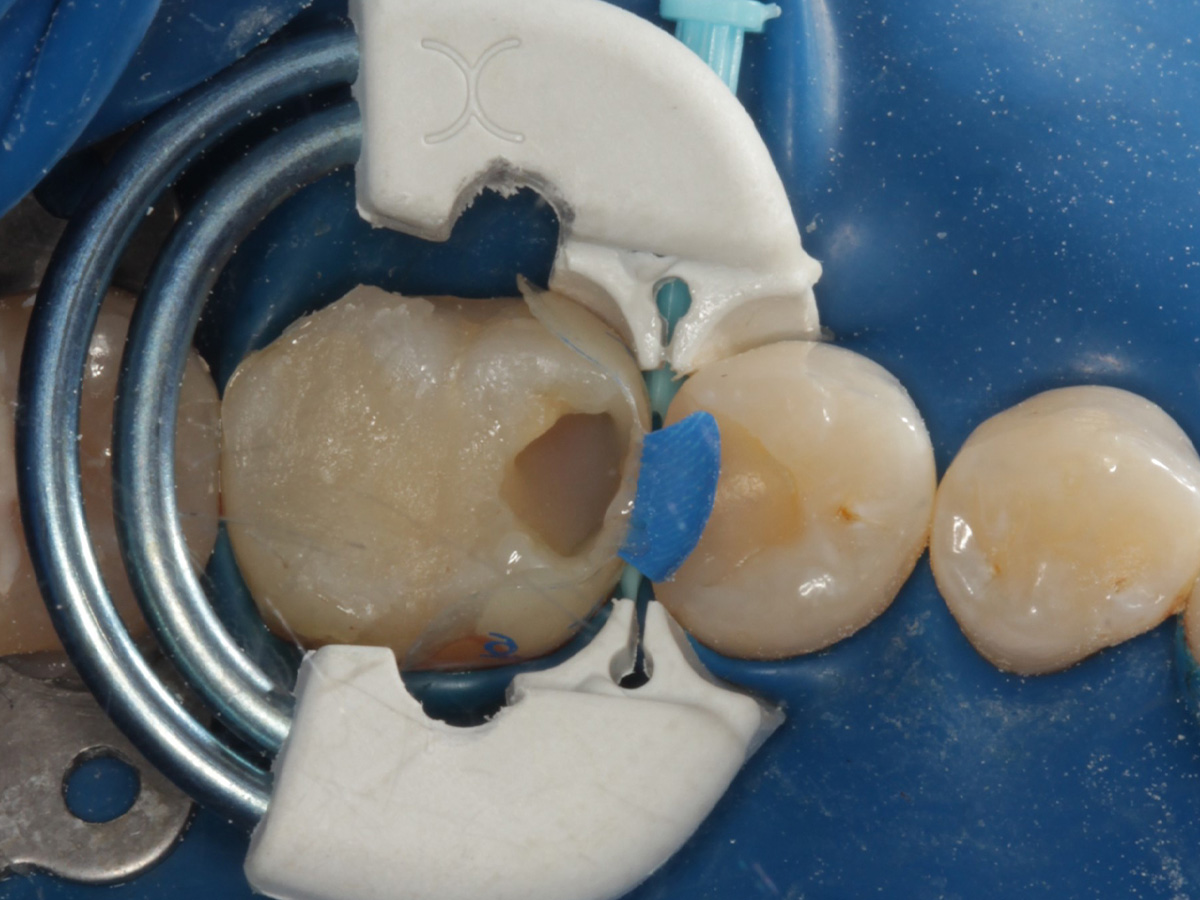

Abbildung 12

Applikation der Matrizen: Evolve Blau Molar 5 mm distal und 6 mm mesial

Abbildung 13

Schmelzätzung bei liegenden Matrizen